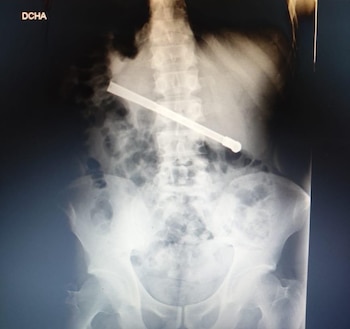

De acuerdo a los datos que recolectó Infobae, Oscar Fabián Rodríguez (35), oriundo de Venado Tuerto, pidió asistencia médica a causa de una dolencia estomacal, y fue llevado de urgencia hasta el hospital, donde se corroboró en una placa radiográfica que había ingerido una bombilla que había quedado atravesada transversalmente en la zona toracoabdominal.